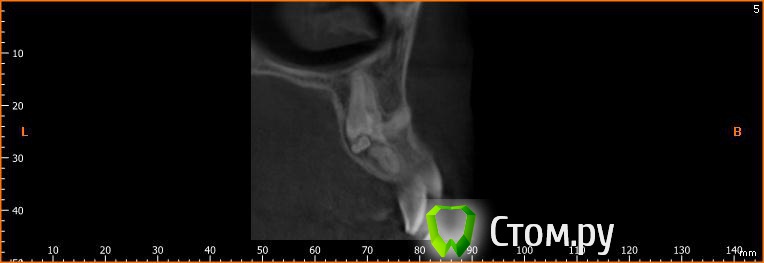

Фазлиев Азат Ильдусович Опубликовано 25 сентября, 2014 Поделиться Опубликовано 25 сентября, 2014 не могу не поделиться)) 4 Ссылка на комментарий

Фазлиев Азат Ильдусович Опубликовано 16 мая, 2016 Автор Поделиться Опубликовано 16 мая, 2016 чем закончился случай?пока только удалением одонтомы Ссылка на комментарий